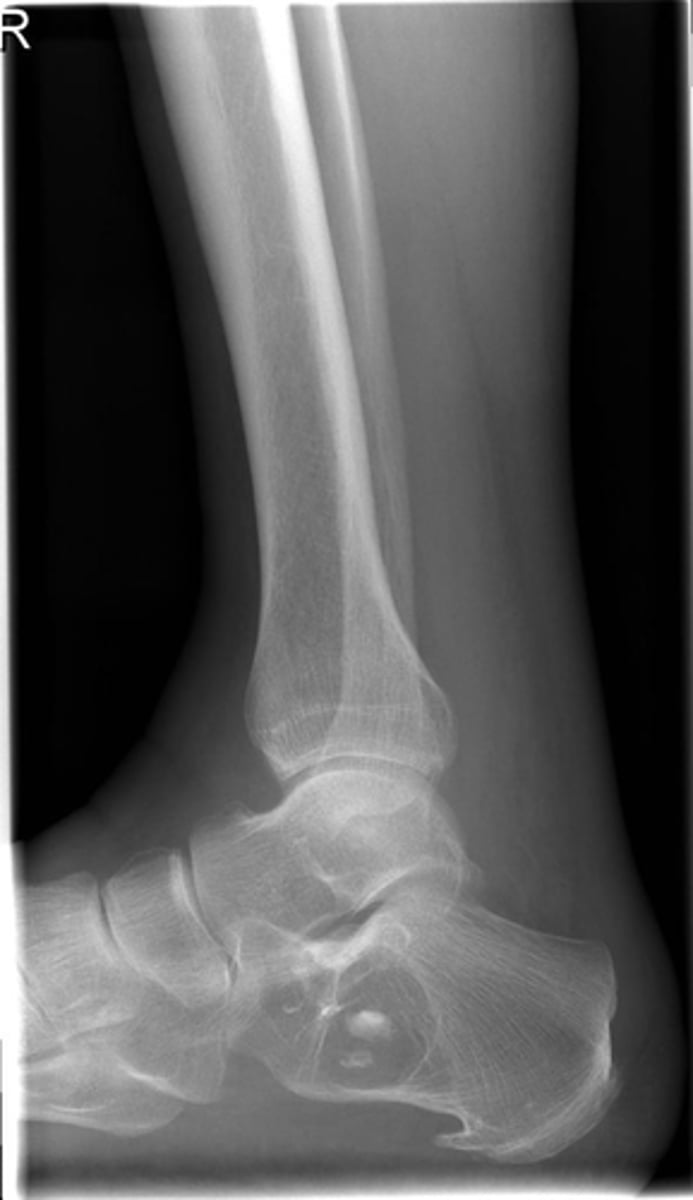

Lateral proximal tibia

Bone

<p>Bone</p>

- Longitudinal: epiphysis/metaphysis (up to joint surface)

- Eccentricity: eccentric

- Transverse: medullary

Location

<p>Location</p>

Monostotic

Mono/polyostotic

<p>Mono/polyostotic</p>

New cards

>1 cm

Size

<p>Size</p>

- Lytic

- Geographic

- Short zone of transition

Behavior

<p>Behavior</p>

- Cortical thinning

- Cortical expansion

Cortex

<p>Cortex</p>

Giant cell tumor

Most likely diagnosis?

<p>Most likely diagnosis?</p>

Refer to orthopedist or oncologist

Next step?

<p>Next step?</p>

Could be aggressive (20%)

Concerns/complications?

<p>Concerns/complications?</p>